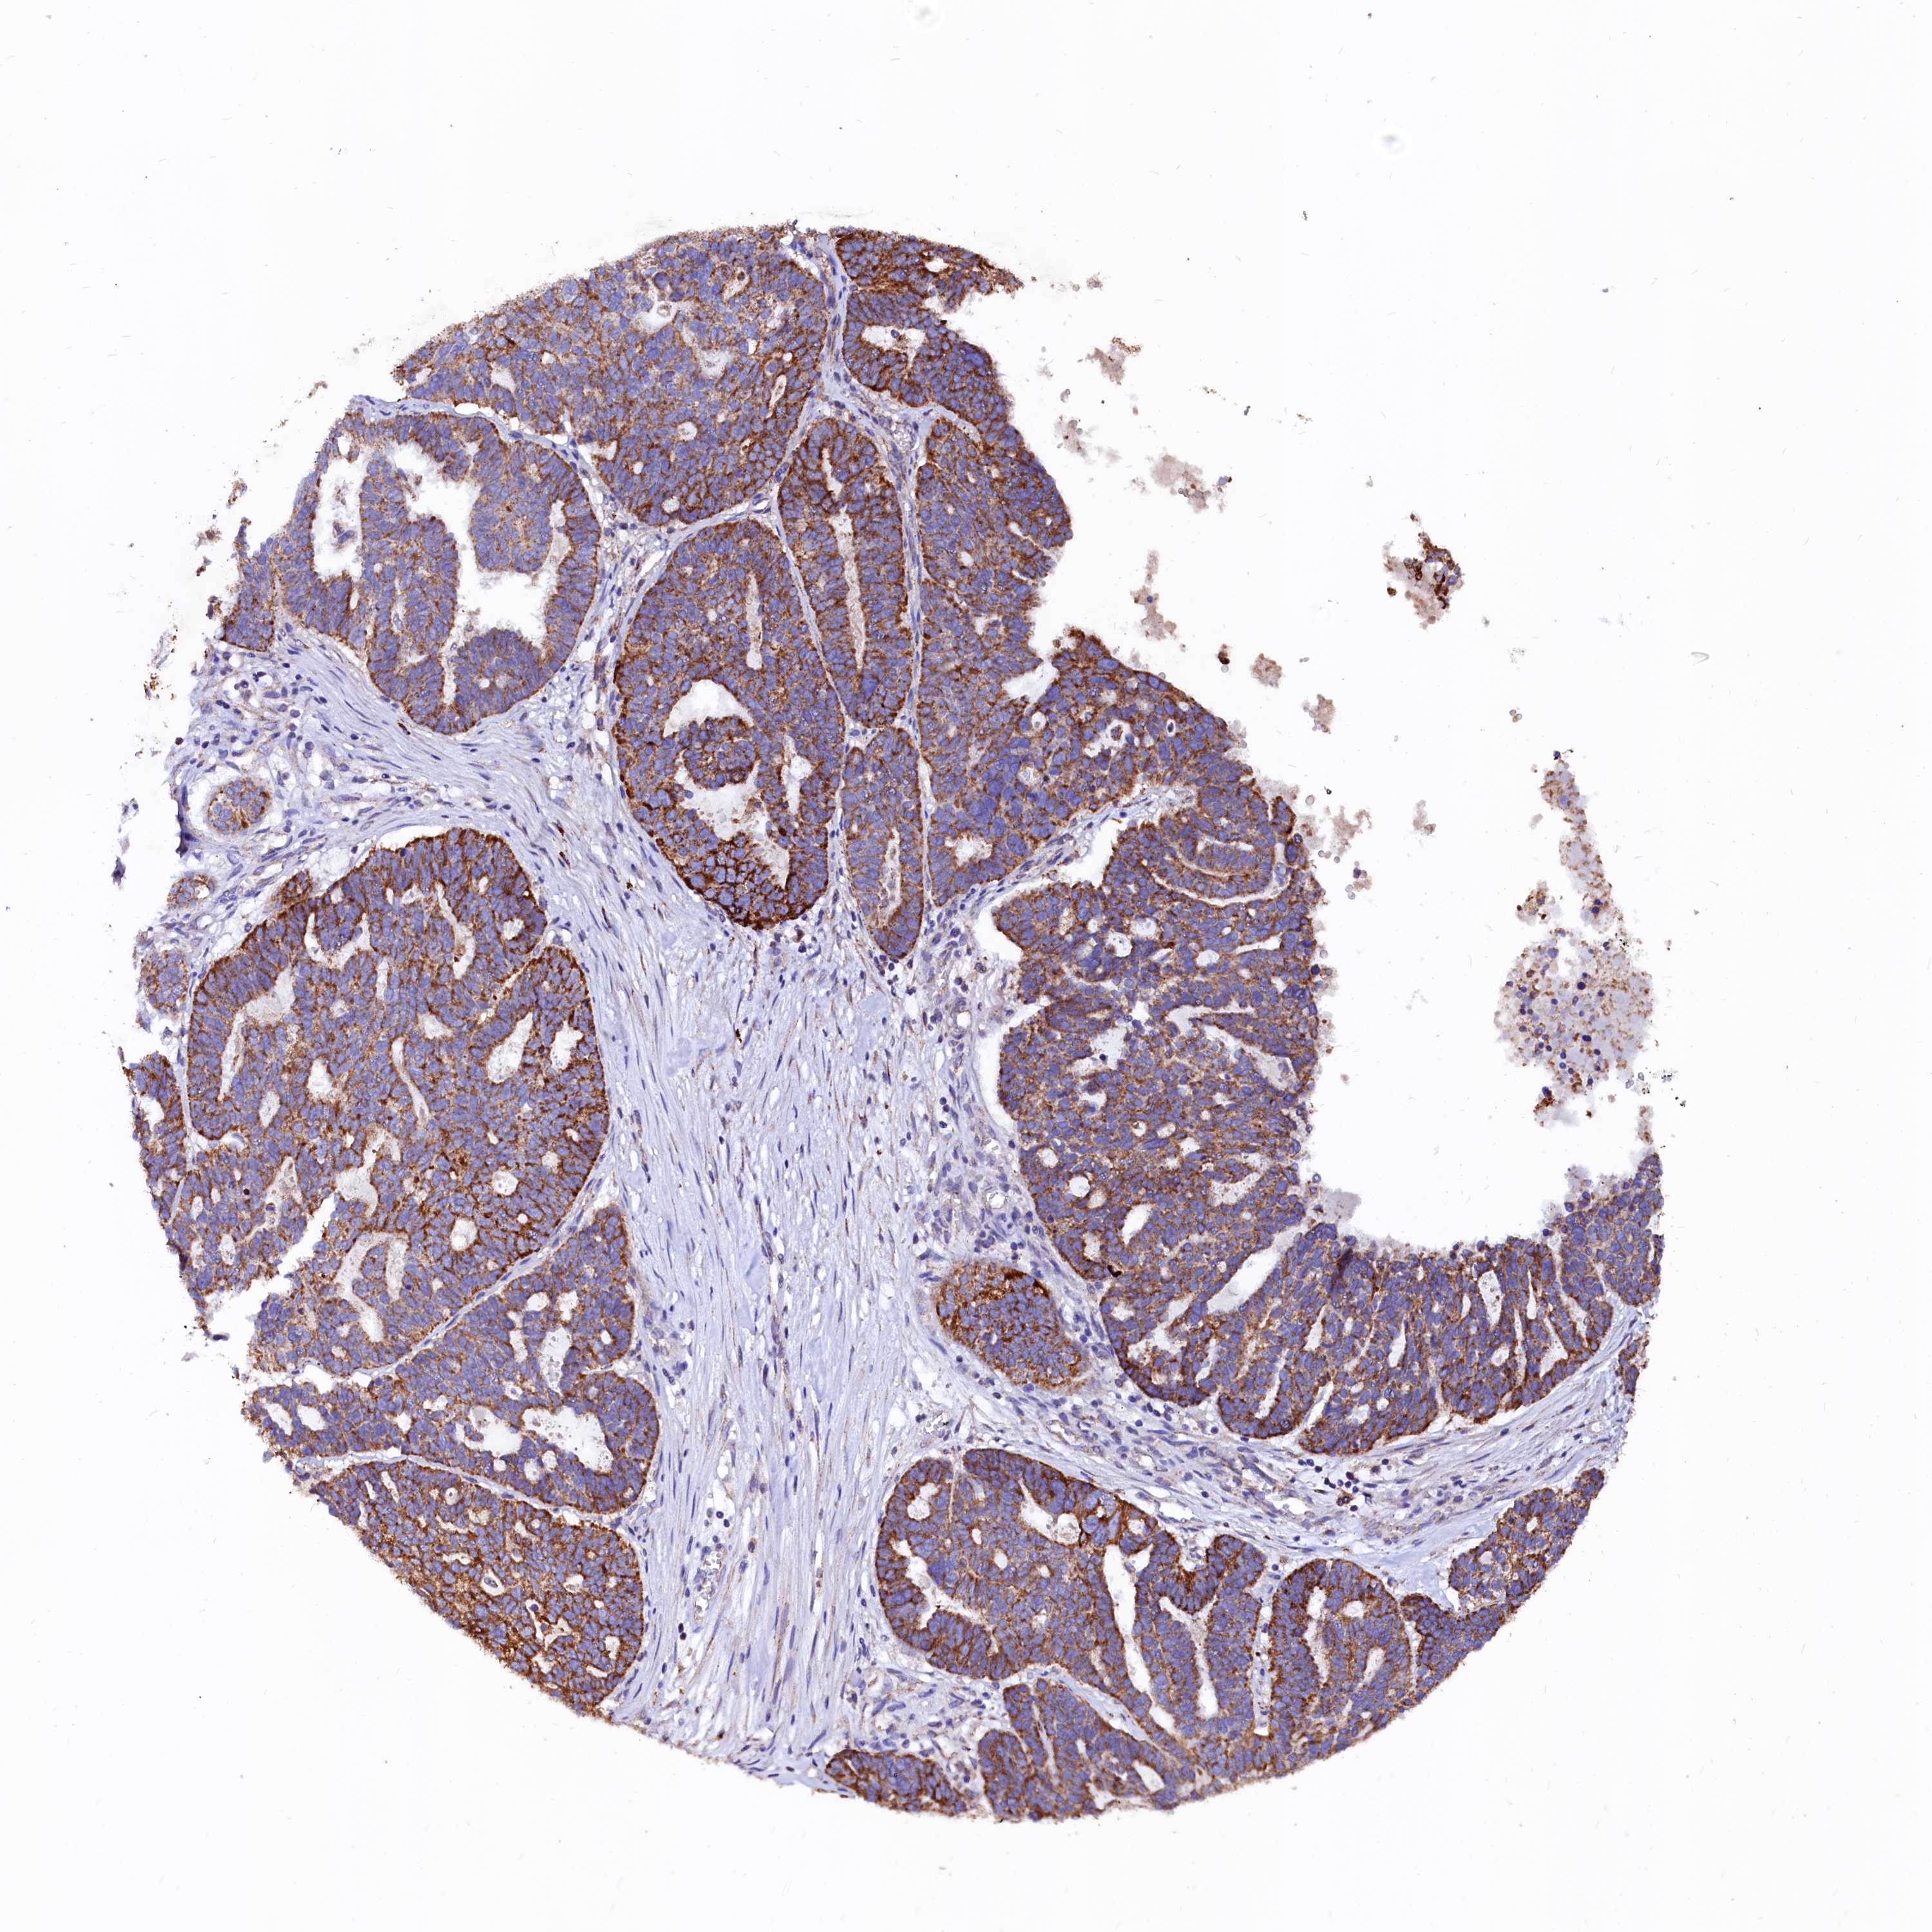

OVARIAN CANCER - Protein expressioni

A mouse-over function shows sample information and annotation data. Click on an image to view it in a full screen mode. Samples can be filtered based on level of antibody staining by selecting one or several of the following categories: high, medium, low and not detected. The assay and annotation is described here.

Note that samples used for immunohistochemistry by the Human Protein Atlas do not correspond to samples in the TCGA dataset.

Antibody stainingi

Antibody staining in the annotated cell types in the current human tissue is reported as not detected, low, medium, or high, based on conventional immunohistochemistry profiling in selected tissues. This score is based on the combination of the staining intensity and fraction of stained cells.

Each image is clickable and will lead to virtual microscopy that enables deeper exploration of all samples and also displays staining intensity scores, fraction scores and subcellular localization as well as patient and tissue information for each sample.

Antibody HPA002328

Antibody CAB037200

Staining

High

Medium

Low

Not detected

Intensity

Strong

Moderate

Weak

Negative

Quantity

>75%

75%-25%

<25%

None

Location

Nuclear

Cytoplasmic/membranous

Cytoplasmic/membranous,nuclear

Cystadenocarcinoma, mucinous, NOS

Carcinoma, endometroid

Cystadenocarcinoma, serous, NOS

Carcinoma, NOS